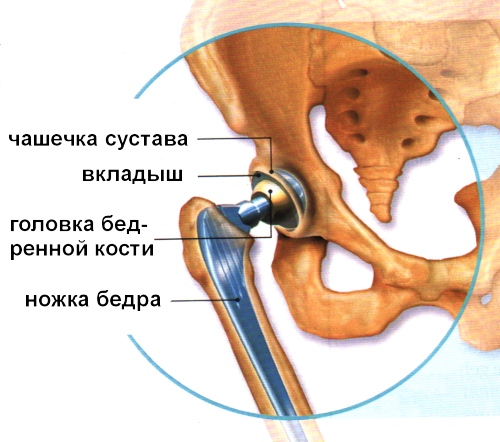

Замена таз сустава

Замена таз сустава 113 фотографий